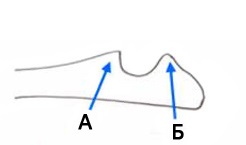

A - koronoid

B - uncinatus

folyamat